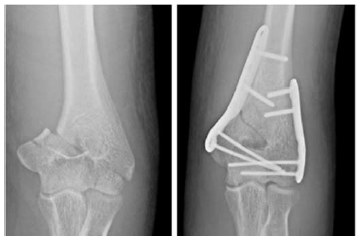

Um paciente de 30 anos de idade foi vítima de queda de árvore há cerca de um dia, sofrendo trauma no cotovelo esquerdo. Foi atendido no pronto-socorro e solicitadas as radiografias retratadas nas figuras.

Considerando o princípio utilizado, espera-se que a consolidação obtida seja

No referido caso clínico, para estabilização absoluta, foi utilizada a compressão interfragmentária usando parafuso

No acesso cirúrgico lateral ao úmero distal, o nervo radial está localizado entre o músculo

Assinale a alternativa que indica a principal ação do músculo braquial.

O músculo braquial é inervado pelos nervos

A inserção do músculo braquial ocorre na(o)

No úmero, o músculo braquial tem origem nos dois terços

No acesso cirúrgico posterior para o tratamento dessa fratura, a estrutura anatômica que deve ser dissecada e afastada para evitar sua tração é o nervo